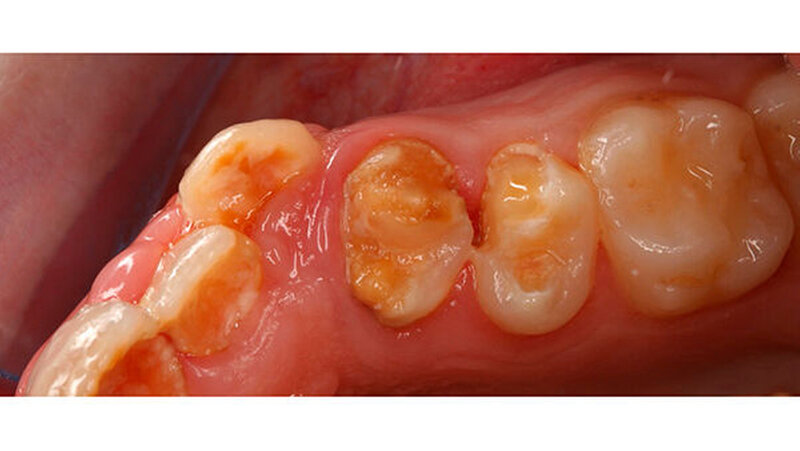

Wie im Fall zur Füllungstherapie ausführlich beschrieben, ist der Haftverbund der derzeit verfügbaren Materialien aufgrund des hypomineralisierten Schmelzes in der Regel nicht zufriedenstellend und oft von einem frühzeitigen Füllungsverlust und/oder einem weiteren Einbruch in den an die Restauration angrenzenden Bereichen begleitet (Abbildungen 9 und 10).

Für kleine und mittelgroße Defekte sind Komposite sehr gut geeignet. Wenig kann zu der Verwendung eines geeigneten Adhäsivsystems gesagt werden, aus einer knapp zehn Jahre alten Untersuchung geht hervor, dass self-etch Systeme möglicherweise den total-etch Systemen überlegen sein können, weil es hier nicht mehr zu Interferenzen nach dem Abspülen kommt. Die größte Schwierigkeit besteht hierbei aber, dass für eine akzeptable Haltbarkeit dieser Restaurationen gefordert wird, die Kavitätenränder in gesunden Schmelz zu legen. Aufgrund des Umfanges der Läsionen sind die Voraussetzungen für diese Maßnahme nur selten erfüllt (vgl.Fallbeispiel auf zm-online). (Abbildung 12).